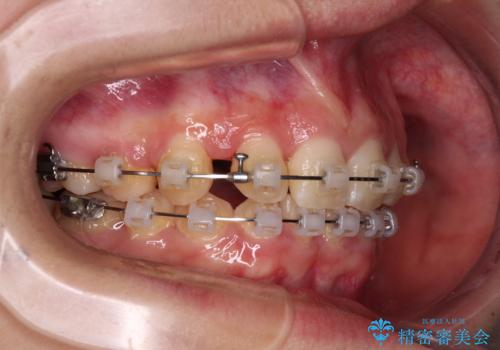

- 矯正装置

- クリアブラケット

上顎左右第一小臼歯2本を抜歯し、ワイヤー装置にて矯正治療を行うこととしました。

通常の抜歯矯正と抜くべき歯の位置が異なるため、咬みにくさが残ってしまうのではないかと懸念されましたが、咬み合わせに違和感なく、スムーズに治療を終えることができました。